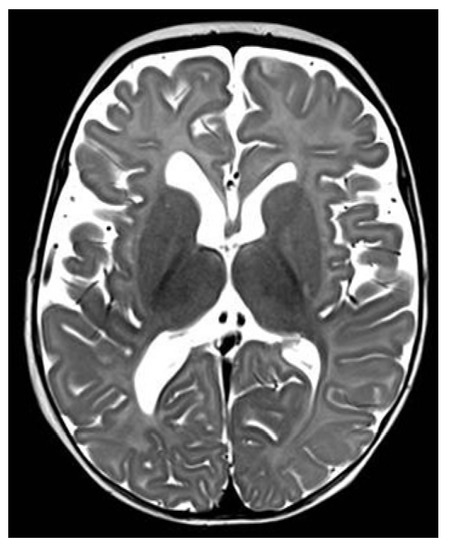

2. Case Description